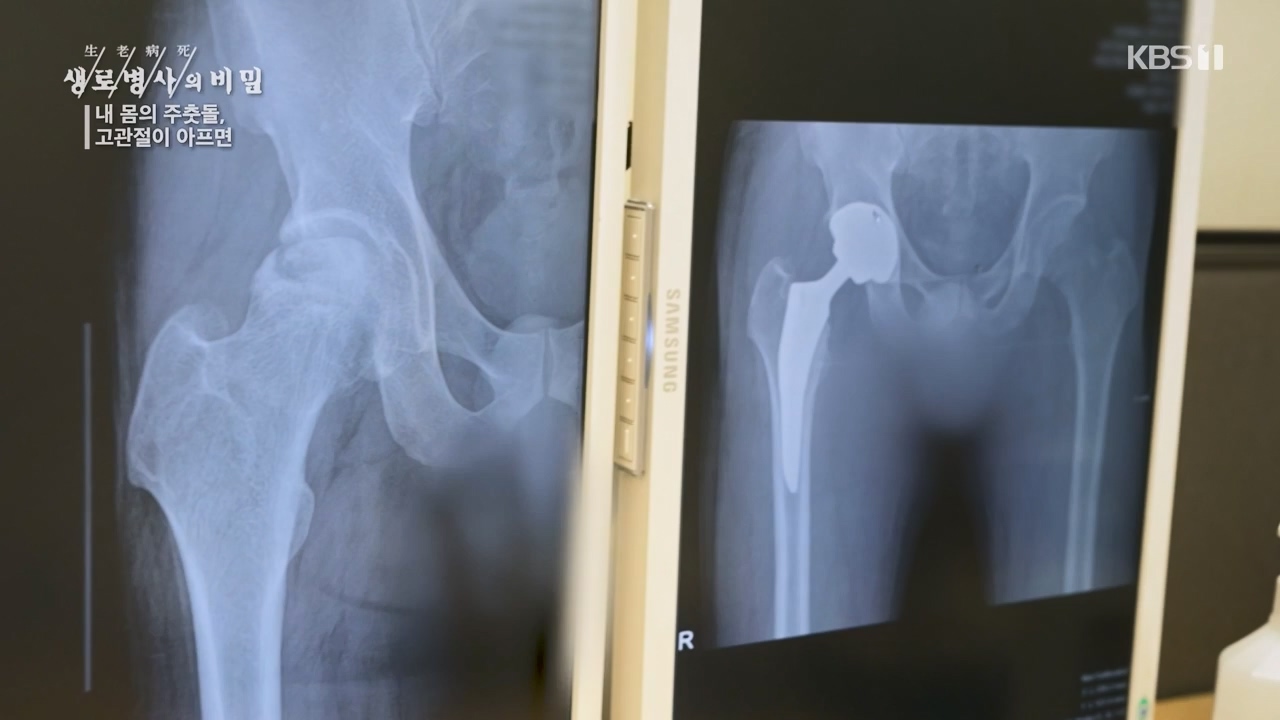

[박은철 기자] 앉고 서고 걷고 달리는 등 우리가 움직이는 순간마다 쉼 없이 일하는 관절이 있다. 엉덩이 관절이라고도 불리는 '고관절'은 상체와...